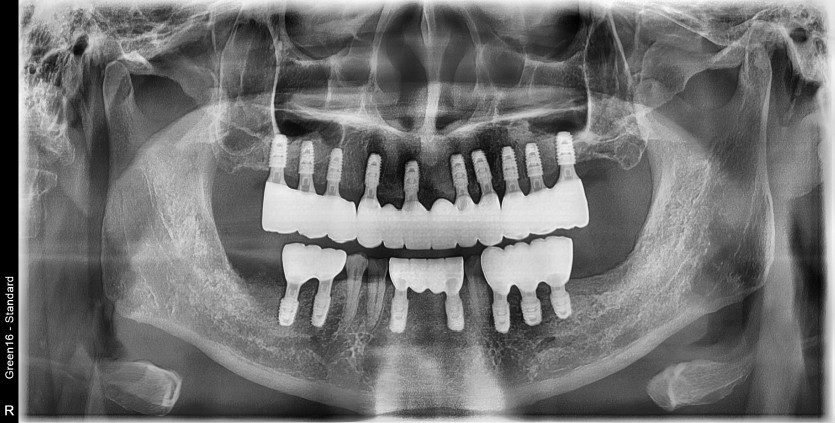

전체 임플란트 증례입니다.

17개의 임플란트로 완성하였습니다